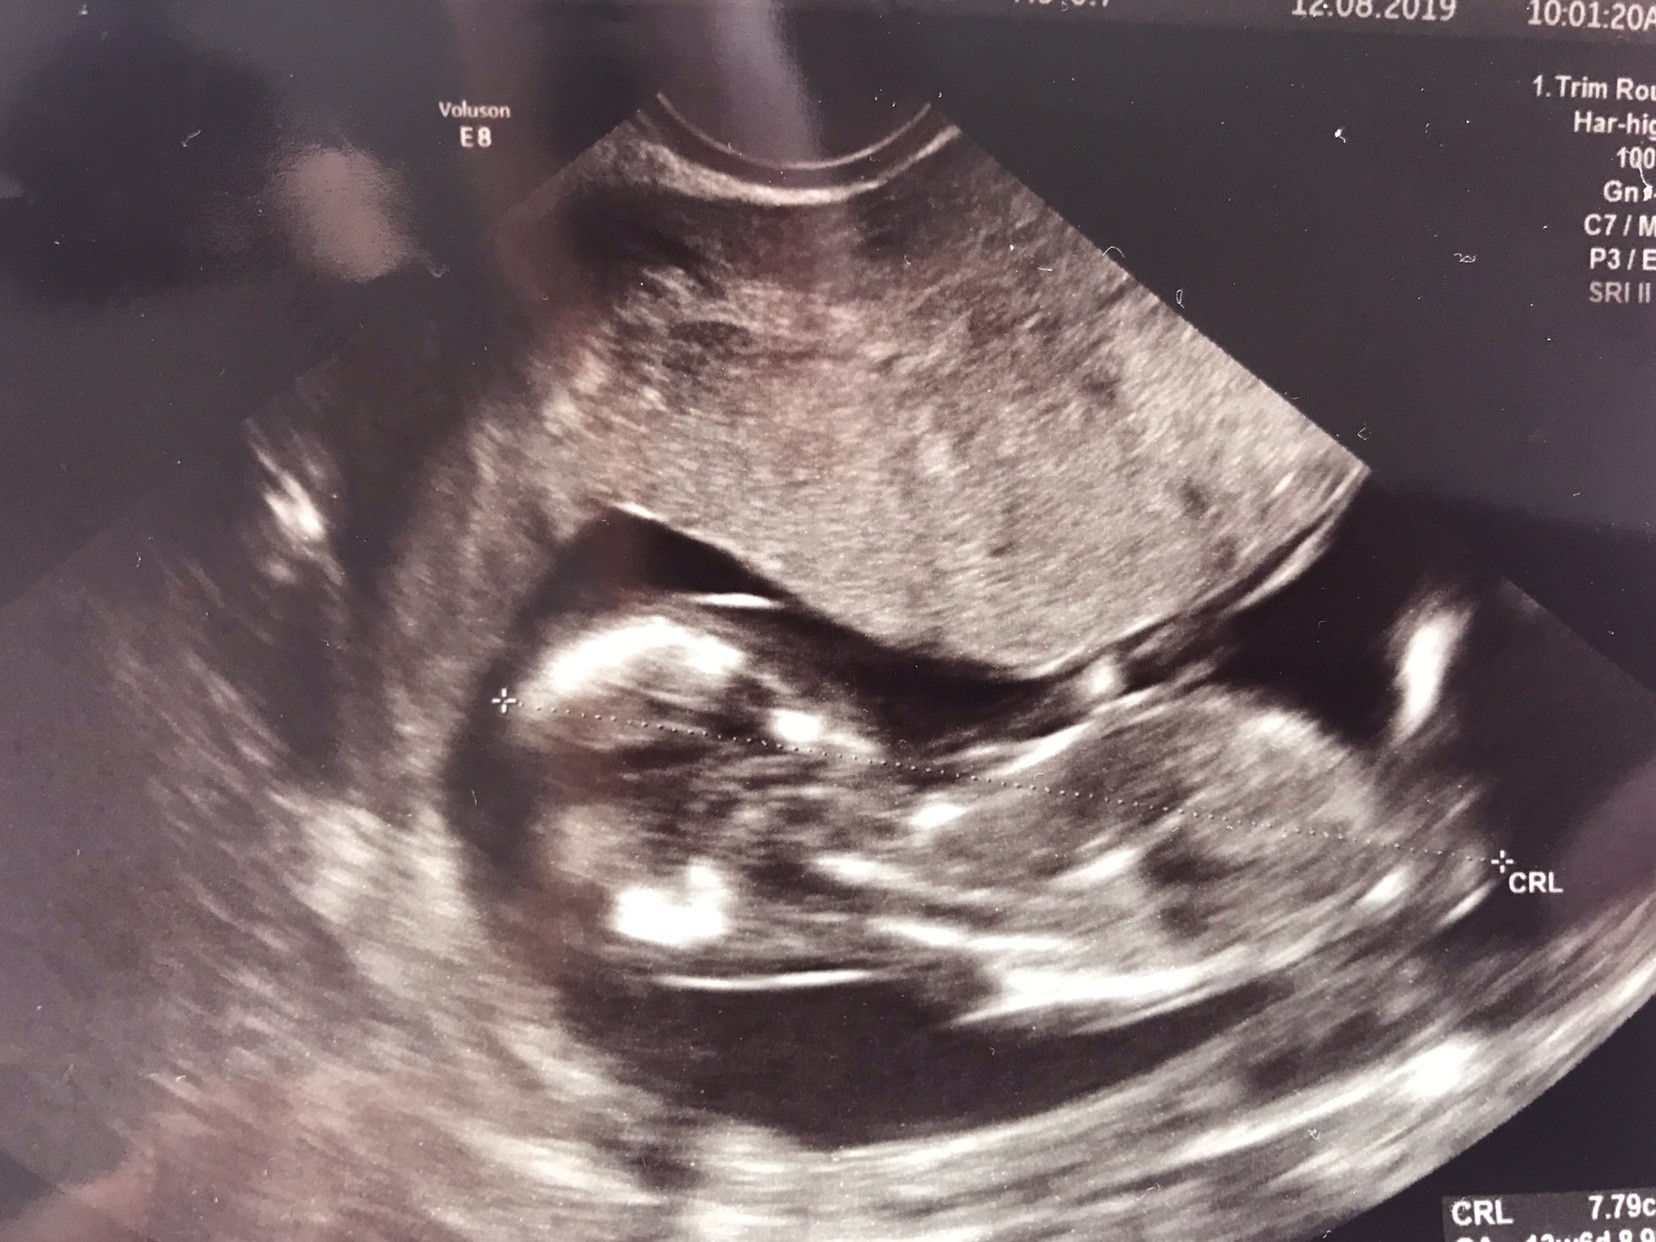

Witam w 19 tygodniu ciąży dowiedziałam się ze będę miała dziewczynkę w 20 tyg okazało się jednak , że to chłopak. Sama już nie wiem bo na jednym usg widać na pewno dziewuche a na drugim chłopca. Może to pempowina ?? Może ktoś mi pomoże rozwiązać ta zagadkę